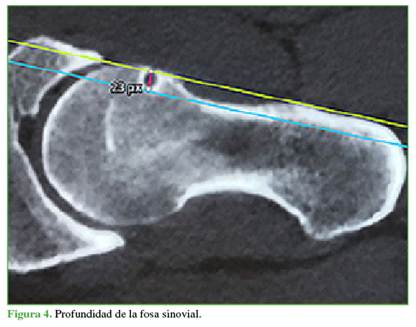

Características morfológicas de la FS: se utilizaron los cortes oblicuos axiales de la TC o la artro-RM para analizar los siguientes parámetros: 1) Profundidad: medida con una tangencial desde el borde anterior femoral y el punto más profundo de la FS (Figura 4); 2) Diámetro: medido con una tangencial desde el borde proximal femoral y el punto más distal de la FS (Figura 5); 3) Forma: redonda, oval o polilobulada y 4) Bordes: completo (quiste) o incompleto (muesca).

La distancia promedio de la FS al centro de rotación de la cabeza femoral fue de 12,5 mm (rango 6-28); la profundidad, de 6,3 mm (rango 2-14); y el diámetro, de 6 mm (rango 2-12). El 82,1% de las FS tenía un borde completo y el 17,9%, bordes incompletos. La forma era redondeada en el 78,6% (22 casos), ovalada en 3 casos (10,7%) y polilobulada en otros 3 casos (10,7%).